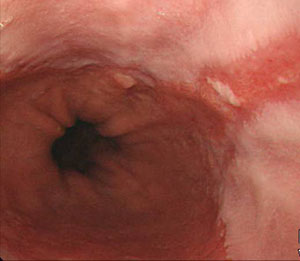

식도는 입과 위장을 연결하는 신체 장기의 일부입니다. 음식물을 섭취하면 식도를 통해 위장으로 전달됩니다. 식도의 이 부분에 암세포가 형성되면 이를 식도암이라고 합니다. 식도는 삼킨 음식물이 위장으로 내려가는 통로이며, 기도와 심장 뒤에 있는 약 35~40센티미터 길이의 관으로 소화 기능은 가지고 있지 않습니다.

일반적으로 식도암은 식도 점막층에서 거의 독점적으로 발생하지만, 의학적으로 식도암은 자궁경부 식도암, 흉부 식도암, 위식도 접합부암 등으로 세분화되며, 식도암 세포의 종류에 따라 편평세포암, 선암, 육종, 림프종, 흑색종 등으로도 나뉩니다.

식도암의 치료는 초기에 발견하는 시기에 따라 많이 달라지는데, 조절이 가능한 경우 내시경 조절 수술을 통해 식도암을 제거하며, 초기인 경우 식도절제술이 평균적으로 표준 식도암 치료법입니다.